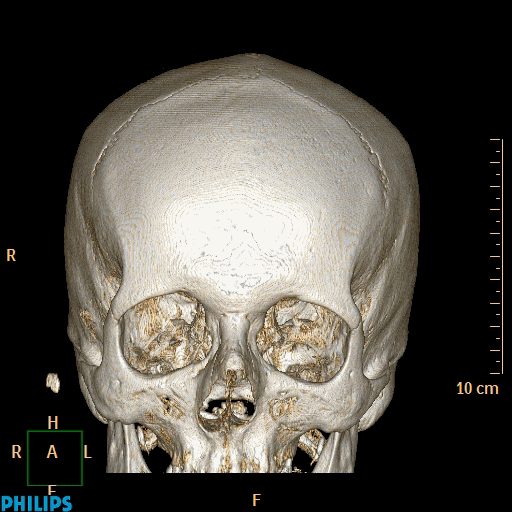

Digital images can be rotated and zoomed easily on the display. distance or relative density can be measured, allowing the identification of the tissue type with ease. Reconstructions in oblique planes (MPR- Multi Plane Reconstruction) or 3D reconstruction can also be obtained from the axial CT and MR images. These reconstructions allow a more accurate characterization of lesions. For example with 3D reconstructions of the digestive system, the inner lumen of the bowels can be visualized , much like an endoscopic examination, without the invasiveness of an actual endoscopy.

Figure 4.: 3D reconstruction of the skull.